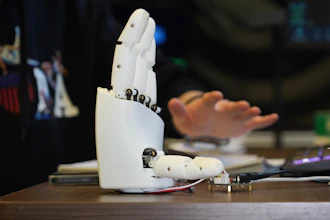

Participants drove a surgical needle through three small holes, first in a virtual simulation and then in a real scenario using the da Vinci Research Kit, an open-source research robot. The exercises mimicked moves needed during surgical procedures on organs in the belly, the researchers said.

“The group that didn’t receive stimulation struggled a bit more to apply the skills they learned in virtual reality to the actual robot, especially the most complex moves involving quick motions,” said Guido Caccianiga, a former Johns Hopkins roboticist, now at Max Planck Institute for Intelligent Systems, who designed and led the experiments. “The groups that received brain stimulation were better at those tasks.”

Robotic surgery systems provide significant benefits for clinicians by enhancing human skill. They can help surgeons minimize hand tremors and perform fine and precise tasks with enhanced vision.